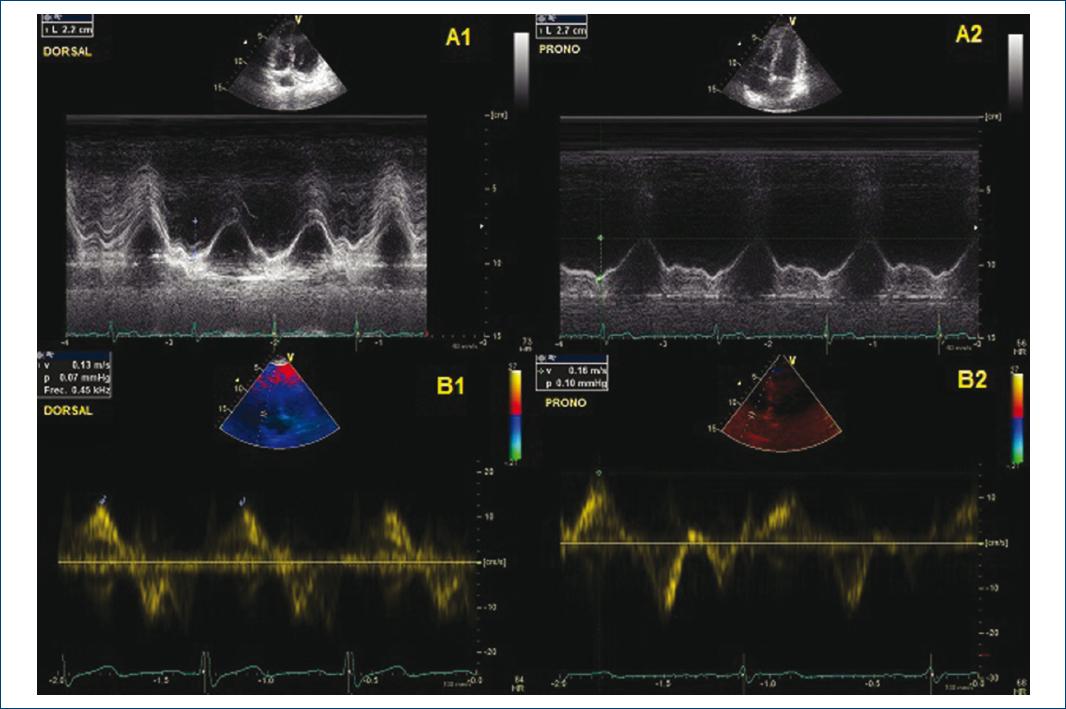

Echocardiographic parameters were quantified according to the guidelines published by the American Society of Echocardiography for assessment of the right heart11,12: tricuspid annular plane systolic excursion (TAPSE), calculated in M-mode in the four-chamber apical plane, measured in millimeters (Fig. 1A1 and A2); tricuspid S1-wave, lateral systolic tricuspid annular tissue velocity, using tissue Doppler in the four-chamber apical plane measured in cm/s, (Fig. 1B1 and B2); RV fractional area change (FAC, %), obtained from RV end-diastolic area in relation to RV systolic area in four-chamber projection, measured as a percentage; pulmonary artery systolic pressure (PAP-s) was calculated with the tricuspid insufficiency (TI) gradient using Bernoulli’s simplified equation: TI2 × 4 + RAP (right atrial pressure) inquired in a four-chamber projection with continuous Doppler, estimated in mmHg; RV/left ventricle (LV) ratio, quantified in four-chamber projection at diastole.

Figure 1 Tricuspid annular plane systolic excursion (TAPSE) echocardiographic images in dorsal decubitus (A1), prone decubitus (A2), and S’-wave in dorsal decubitus (B1), prone decubitus (B2). Dorsal and prone decubitus TAPSE, in M mode and measured in mm. S’-wave, with tissue Doppler, measured in cm/s.